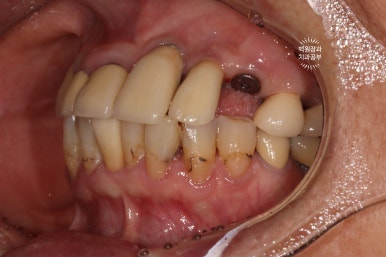

처음 오셨을 때 정면 사진입니다.

잘 보시면, 아까 보였던 치과용 파노라마 사진대로 뿌리만 남은 두 개의 치아를 찾아보실 수 있으실거에요. ㅎㅎ

제가 서두에서 어금니에 스트라우만 임플란트가 많다고 말씀드렸는데, (나머지도 branemark 제품으로 보이며, 명품으로 주름잡던 스웨덴 임플란트 입니다.) 이 미친 퍼포먼스의 스위스 임플란트는 20년이 지난 지금도 짱짱한 성능을 자랑하고 있답니다.

아까 말씀드렸듯, 왼쪽 위 송곳니와 오른쪽 아래 작은어금니에 뿌리만 있는 잔존치근이 관찰됩니다.